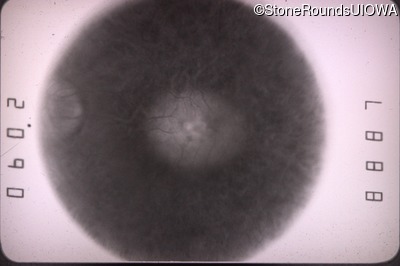

Goldmann Visual Field - Right - 20/70

Exemplar